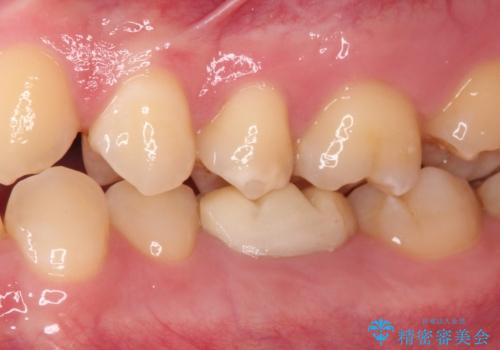

- 食事の度にクラウンにこびりつくとのことで来院された患者様です。

以前の医院では治療終了と言われたそうですが、即席で製作した仮歯が装着された状態でした。

患者様と相談し、根管治療を再度行った後、フルジルコニアクラウンにて補綴治療することとしました。